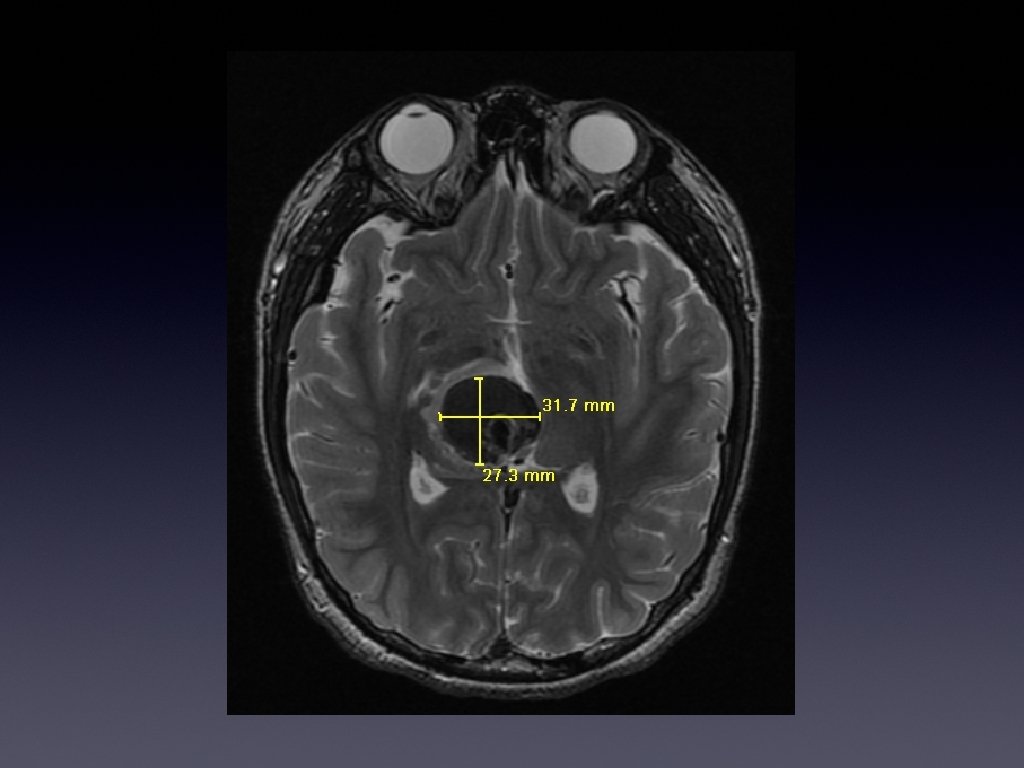

MR No enhancement or feeding/draining vessels

Benign vascular lesion and clot Consistent with cavernous malformation POD 7 - Mild LUE drift, resolved parasthesiae